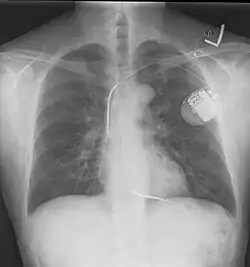

A normal posteroanterior (PA) chest radiograph of someone without any signs of injury. Dx and Sin stand for "right" and "left" respectively.